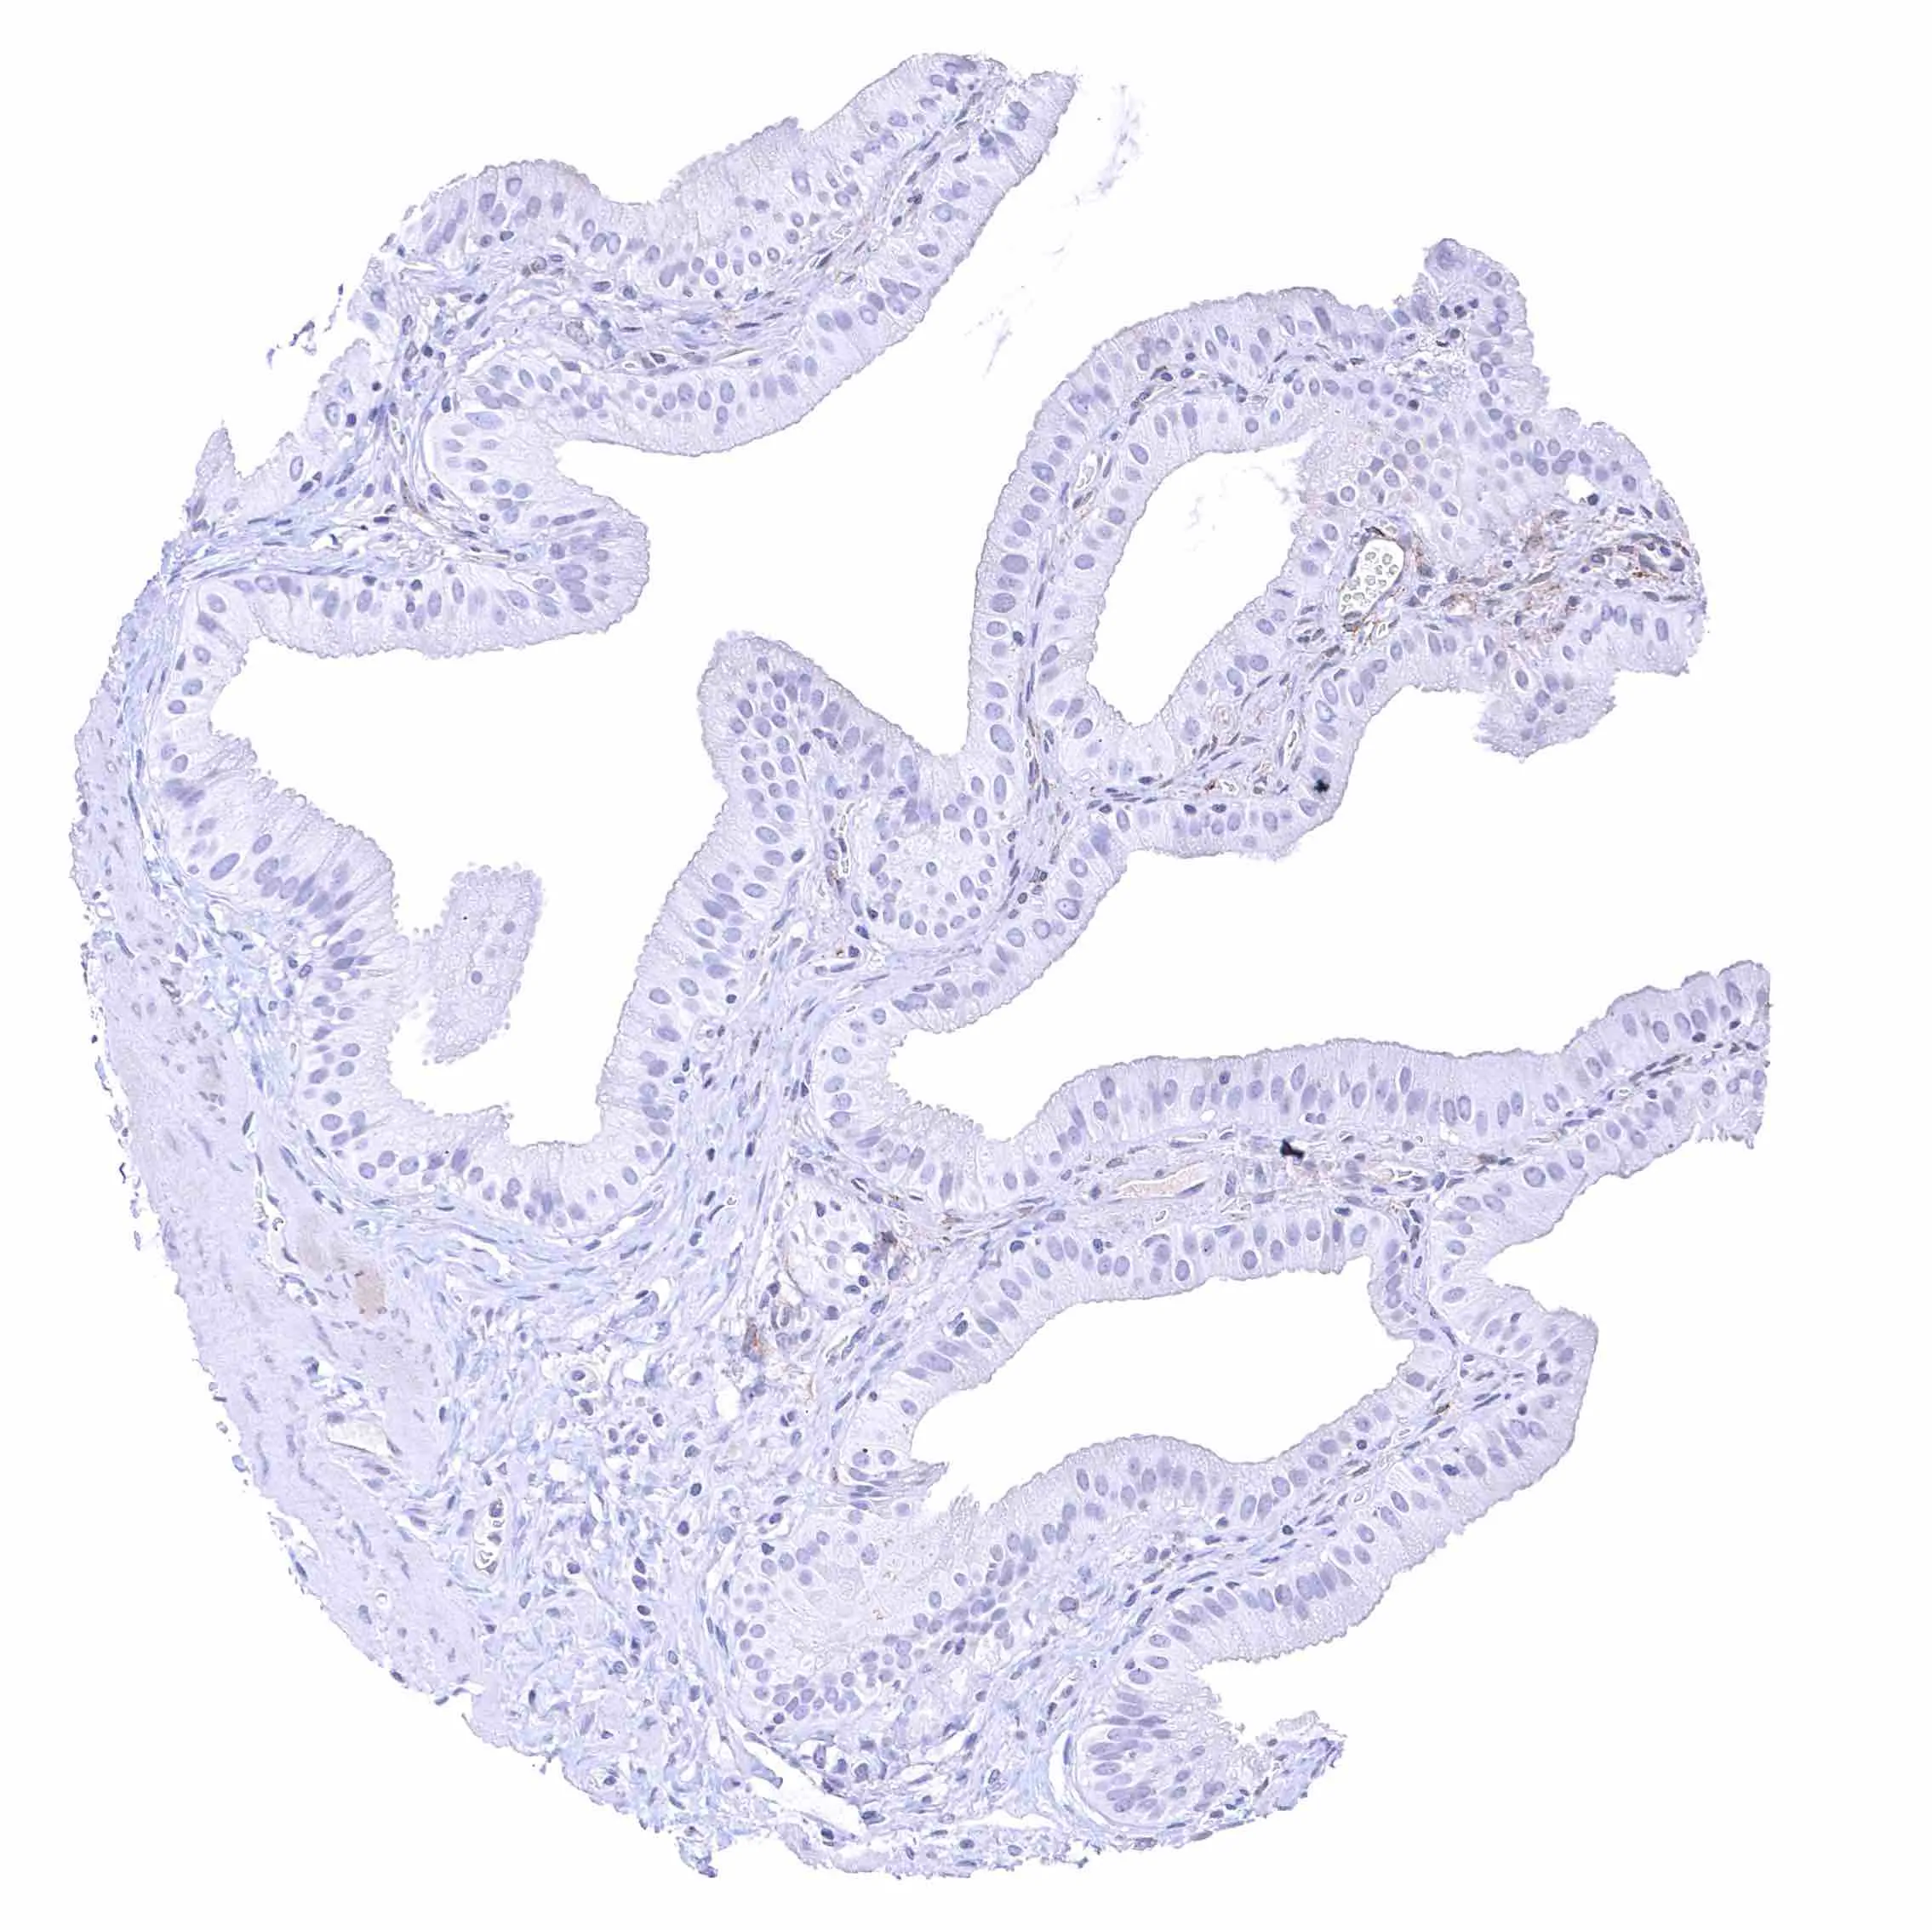

Uterus, endocervix